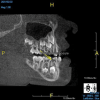

(4.) In a CBCT image axial view, the MB1 and MB2 canals are readily visible in tooth No. 14, and in the coronal view, these two separate canals can be seen to merge into a single apical opening.

(5.) In a CBCT image axial view, the MB1 and MB2 canals are readily visible in tooth No. 14, and in the coronal view, these two separate canals can be seen to merge into a single apical opening.

Being able to see the number and shape of the canals accurately prior to treatment is the desire of any clinician who performs endodontics. Research suggests that, due to improved diagnostic accuracy, the final treatment plan may change in up to 50% of endodontic cases if CBCT is used rather than traditional 2D imaging.14,15 The question of whether or not a patient has an MB2 canal can be answered prior to opening the access preparation (Figure 4 and Figure 5). Visualizing single canals that bifurcate in the apical or middle third of the root or those that merge to a single apical opening can help clinicians to understand their instrumentation needs in advance. In addition, the ability to measure the length and shape of a canal planned for instrumentation prior to utilizing an apex locator helps to confirm any measurements obtained by other means. It should also be noted that the ability to see a pathosis in 3 dimensions and to involve the patient in understanding his or her condition prior to any decision-making allows for definitive treatment planning. In fact, many patients have pathoses associated with teeth that are asymptomatic that remain unknown to them until they are visually presented with the evidence (Figure 6).